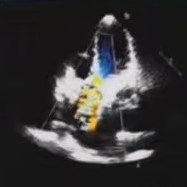

超声检查

• 左右心室及左心房增大

• 主动脉瓣重度关闭不全

• 风湿性心脏病

• 二尖瓣重度狭窄并轻微关闭不全

• 三尖瓣中度关闭不全

• 肺动脉瓣轻度反流

• 中度肺动脉高压

• 左室射血分数(LVEF):55%

• 左室收缩末期内径:38mm

• 二尖瓣瓣口面积:0.55cm²

术后评估

人工瓣膜在主动脉瓣处锚定释放后,工作正常,造影未见瓣周漏,零压差,二尖瓣瓣口面积从0.55cm²恢复至1.2cm²以上,患者血流动力学得到明显改善,手术圆满完成,患者苏醒后顺利转入病房。

此案例中,唐秀革院长、莫昌干主任手术团队先为患者施行PBMV,再借助VitaFlow Liberty™电动可回收瓣膜输送系统进行TAVR,术后造影检查和心脏彩超评估人工瓣膜位置佳,活动良好,主动脉瓣跨瓣压差为零,无瓣周漏现象。患者心功能得到显著改善,手术取得圆满成功。此次手术的成功开展彰显了TAVR治疗主动脉瓣反流的安全性和有效性,也表明河池市人民医院心脏瓣膜团队手术技术的不断精进与成熟,为辖区内高龄、复杂心脏瓣膜疾病患者带来了治愈的希望。